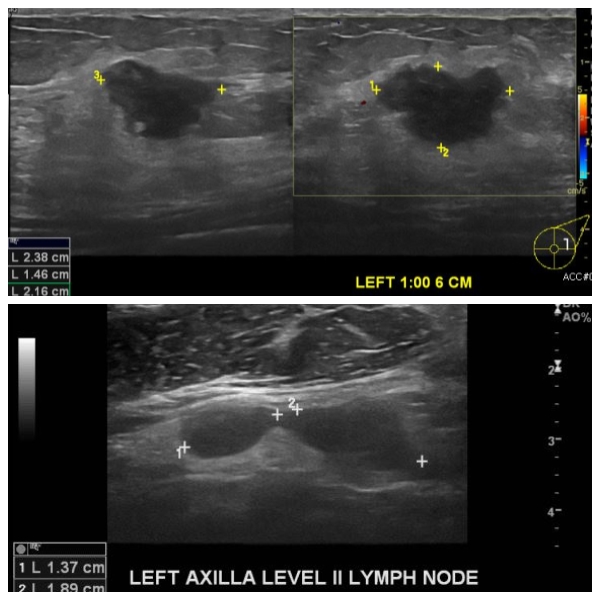

건강검진상 이상 소견으로 내원하신 50대 여성분으로  좌측 1시 방향에서 6cm 떨어진

거리의 혹 조직검사 시행하여 침윤성 유관암 진단 되었으며 좌측 겨드랑이 림프절 비대

세침검사 시행하여 전이암의로 진단 되었습니다.